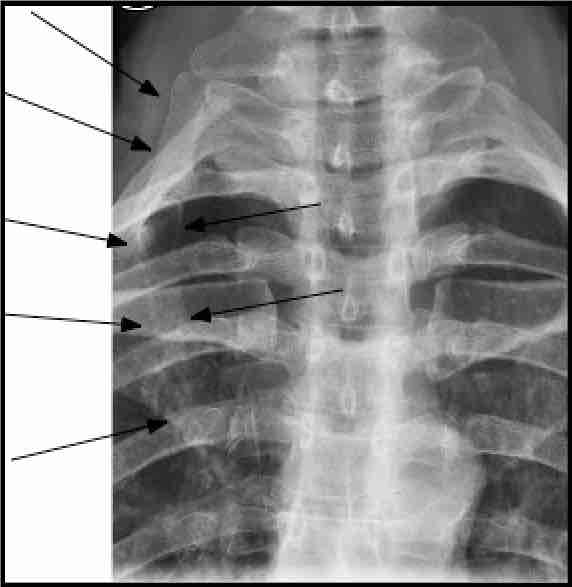

A cervical rib, very occasionally an apical lung tumour (Pancoast, for example), or scar tissue from old injuries may invade the interscalene space. Old fractures of the first rib, or the clavicle may set up compression of the artery or nerves as scar tissue grows around the fractured bone.

About 2 people per thousand have an extra cervical rib, located above the normal first thoracic rib. This cervical rib penetrates through the inter scalene triangle, taking up space and when large can produce severe signs and symptoms in the arm.